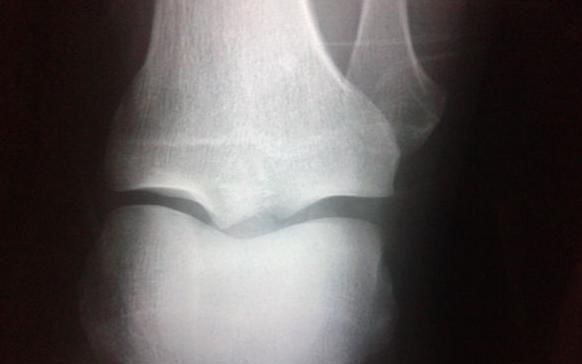

前两天听到一件痛心的事情,老家亲戚的孩子今年8岁了,从小个头就比较高。亲戚也一直引以为豪,经常说孩子小时候就应该多补身体,这样才能长得高。但是前两天突然发现孩子胸前竟然发育了,这也吓坏了亲戚,抓紧带着孩子到了医院检查。

检查结果出来之后,医生说孩子骨垢线已经闭合了,应该是营养过剩导致孩子性早熟了。这也让亲戚感到后悔,孩子虽然现在比同龄娃要高,但是骨垢线闭合也意味着孩子以后不会再长了,直接影响到孩子的未来。